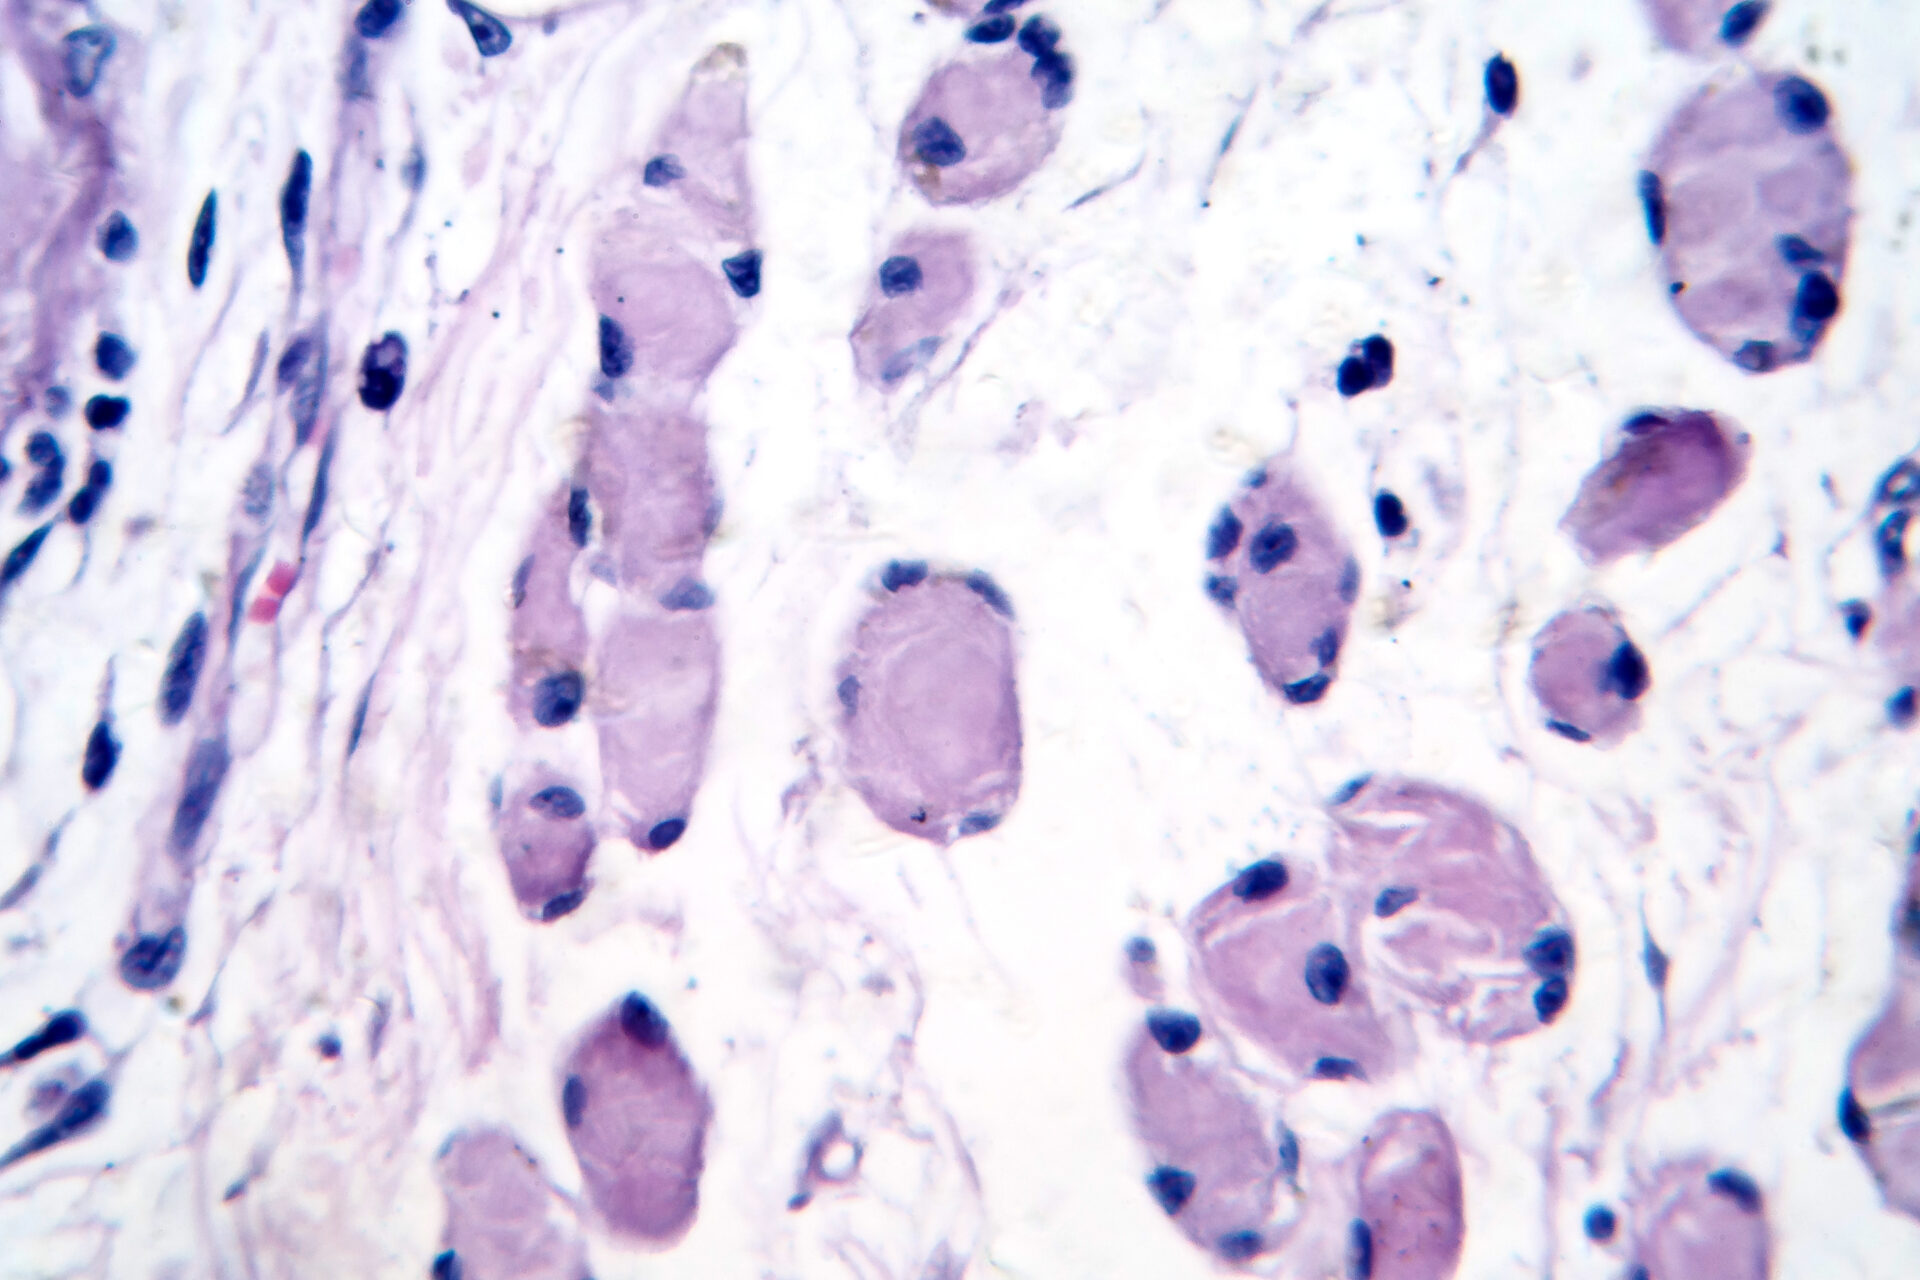

Skeletal muscle atrophy (Adobe Stock)

Photomicrograph showing decreased fiber size with increased spacing between them, reduced myofibrils, increased endomysial connective tissue with fatty infiltration.